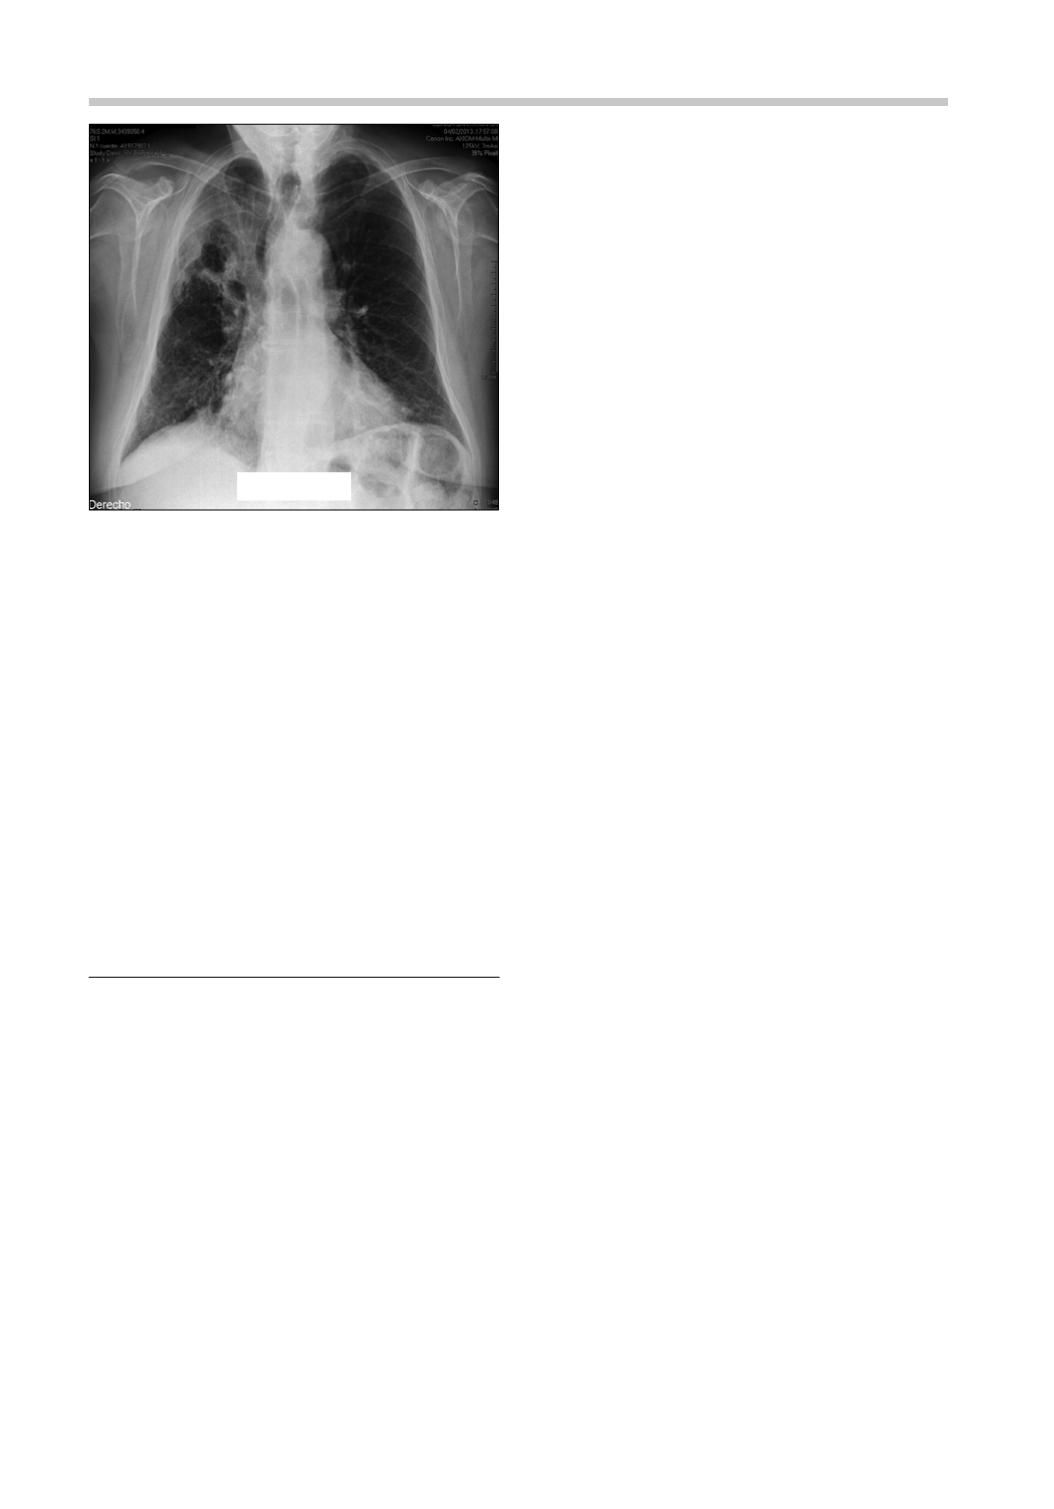

en su tercer mes. La radiografía actual (Figura 5)

muestra en el lóbulo superior derecho una lesión

residual cavitada de menor tamaño y regresión de

opacidades pulmonares basales.

Figura 5.

Radiografía de tórax al 3

er

mes de tratamiento

antibiótico oral. Destaca regresión del tamaño de la ca-

vidad del lóbulo superior derecho y la desaparición de

opacidades basales bilaterales.